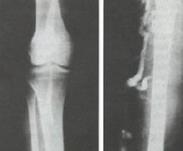

先天性靜脈畸形肢體肥大綜合征(Klippel-Trénaunay syndrome,KTS)是一種復(fù)雜的先天性血管發(fā)育異常疾病。臨床以深部和(或)淺部靜脈發(fā)育畸形,皮膚血管瘤(痣),骨骼和軟組織過(guò)度生長(zhǎng)等三聯(lián)征為特征。少數(shù)病例可伴有肢體軟組織海綿狀血管瘤和內(nèi)臟器官的血管瘤,個(gè)別患者可并發(fā)動(dòng)脈病變。